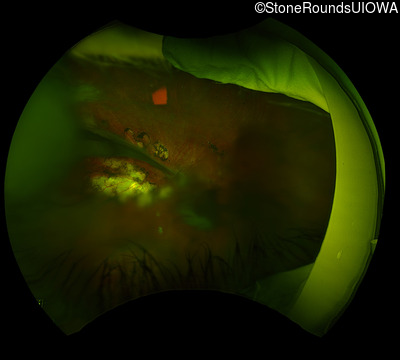

Visit at age: 12 years (Visit 2)

B-Scan Ultrasonography - Right - 20/600

Exemplar

B-Scan Ultrasonography - Left - 20/300